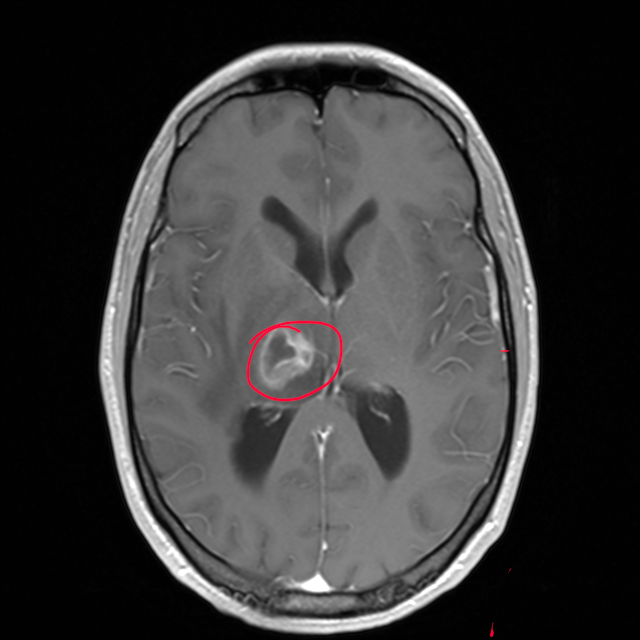

Anfang Oktober letzten Jahres hat sich mein Leben ziemlich abrupt verändert. Was zuerst wie eine Anomalie im Gehirn aussah, stellte sich am Ende als zerebrale Toxoplasmose heraus. Seitdem habe ich eine Hemiparese auf der linken Seite – heißt konkret: Die komplette linke Körperhälfte ist stark eingeschränkt.

What first appeared to be a brain anomaly was diagnosed as cerebral toxoplasmosis, leaving me with left-sided hemiparesis. Everyday tasks now require immense effort, and I’m currently unable to work or earn an income.